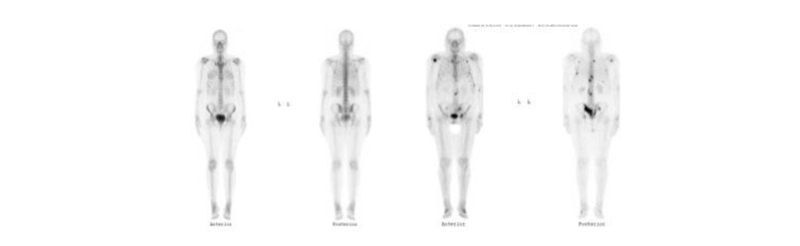

Cintigrama óseo

El cintigrama óseo permite la obtención de un mapa de la actividad osteoblástica de todo el esqueleto. Esto se logra mediante la administración endovenosa de un compuesto difosfonado marcado con Tecnecio-99m. Las moléculas que más utilizadas son el metilén-difosfonato (MDP) y el hidroxi-metilén-difosfonato (HMDP), siendo el primero el que por lejos predomina. Luego de la administración del radiofármaco por una vía periférica se espera entre 2 y 4 horas para obtener las imágenes una vez que el trazador se haya fijado en el esqueleto. Estos compuestos se absorben sobre la superficie de los cristales de hidroxiapatita, los cuales se encuentran más expuestos en el hueso de neoformación y más abundante en aquellos sitios en que existe importante recambio óseo, lo que producirá una mayor concentración del trazador radioactivo.

La técnica presenta una alta sensibilidad para la detección de lesiones osteoblásticas, pero una baja especificidad, dado que cualquier patología que genere un mayor recambio óseo provocará una hipercaptación del difosfonato. La alta sensibilidad ha hecho que el cintigrama óseo de cuerpo entero constituya un examen ideal para la detección de metástasis óseas osteoblásticas, como las que ocurren en la mayoría de las lesiones derivadas de un cáncer de próstata.

La probabilidad de compromiso óseo es de menos del 1% en los cánceres con APE<10 ng/ml y ausencia de síntomas de dolor esquelético, y por otro lado es de alrededor de 50% si el APE es >40 ng/ml. Por lo tanto para etapificación inicial se debería solicitar un cintigrama óseo en todo cáncer de próstata con APE>20 ng/ml. El grado de Gleason también se correlaciona con la probabilidad de metástasis en el cintigrama óseo (Gleason menor de 7 v/s Gleason mayor o igual 8) (37,38). En el seguimiento se utiliza el cintigrama óseo para evaluar la presencia de metástasis óseas en caso de elevación de los valores de APE o si aparece dolor óseo sin otra causa que lo explique (39).